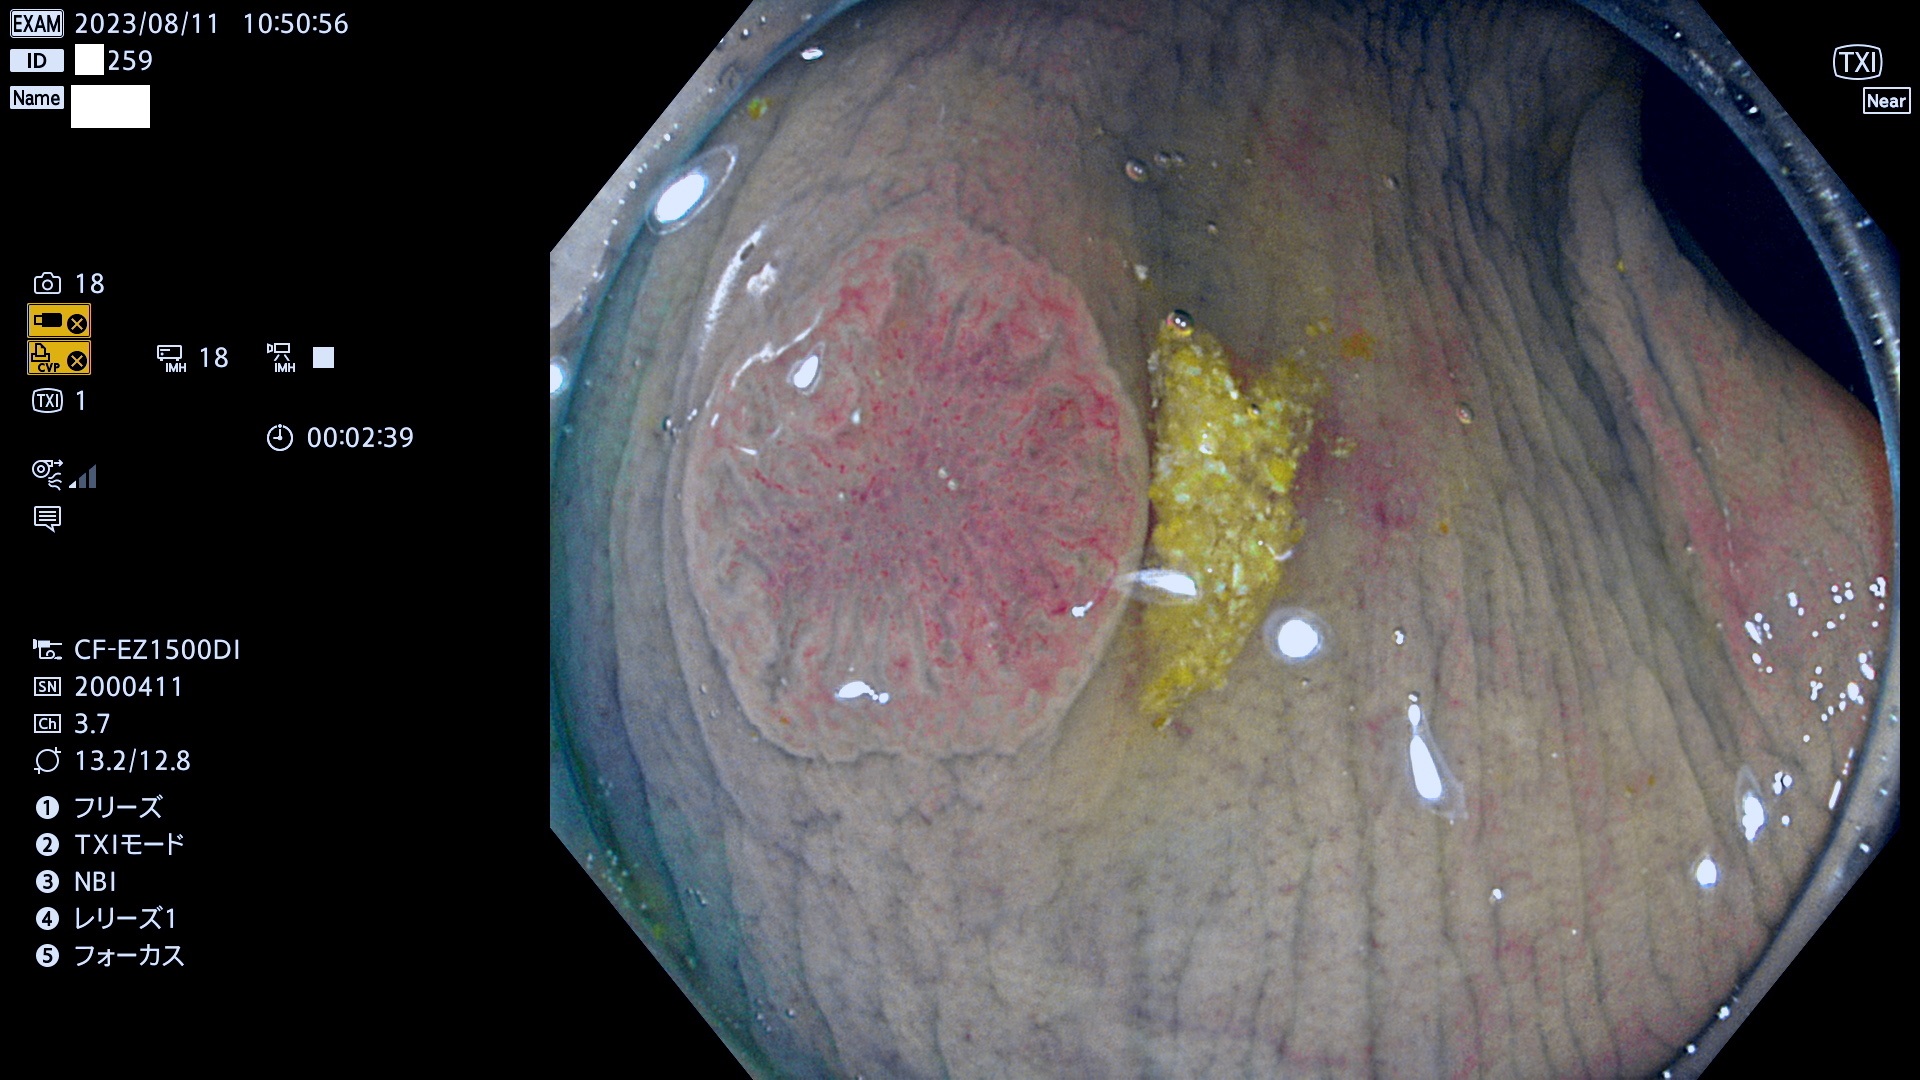

今週のUb、Uc型腺腫

表面型腺腫(Flat Adenoma)の中で、完全に平坦な物をUb、陥凹している物をUcと呼びます。平坦隆起型(Ua)よりも、発見が難しく危険な病変です。このタイプは「内視鏡後・大腸癌の重要犯人」であり、この発見率は「腺腫発見率」よりも、重要な意味があります。

毎週の検査(木・金・土・日)に発見されたUb、Uc型・腺腫を、その週の日曜の夜にUPし1週間、提示します。

抽出の対象期間 2023年8月10日(木)〜8月13(日)の4日間(48件の検査)11件